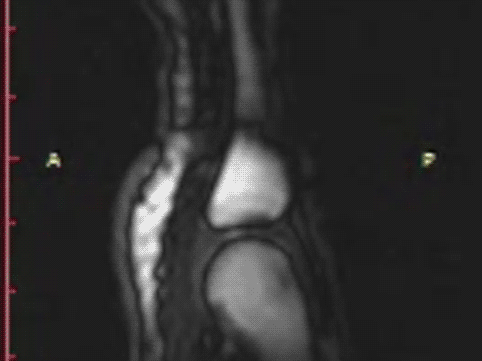

캐나다 앨버타 대학교 연구진이 MRI를 사용해

손가락 꺽기 할 때 관절이 어떻게 되는지 실험해 봤어.

그랬더니 의외로 이 소리는 뼈와 뼈가 떨어지며

생긴 빈 공간에 공기가 들어오며 생긴 소리였다는 거야.